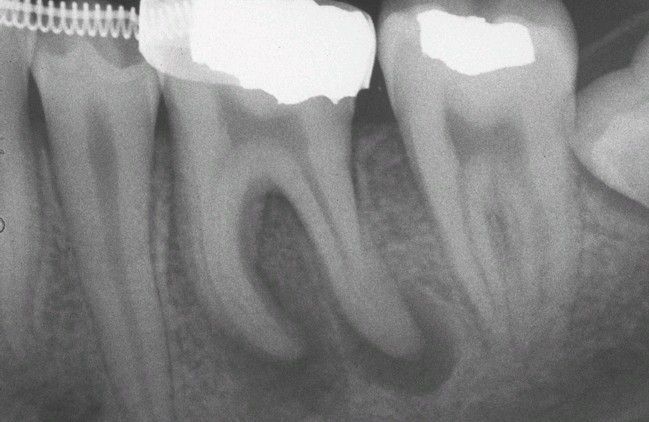

Periapical Granulomas.

Discrete periapical radiolucencies associated with the apices of the mandibular first molar.